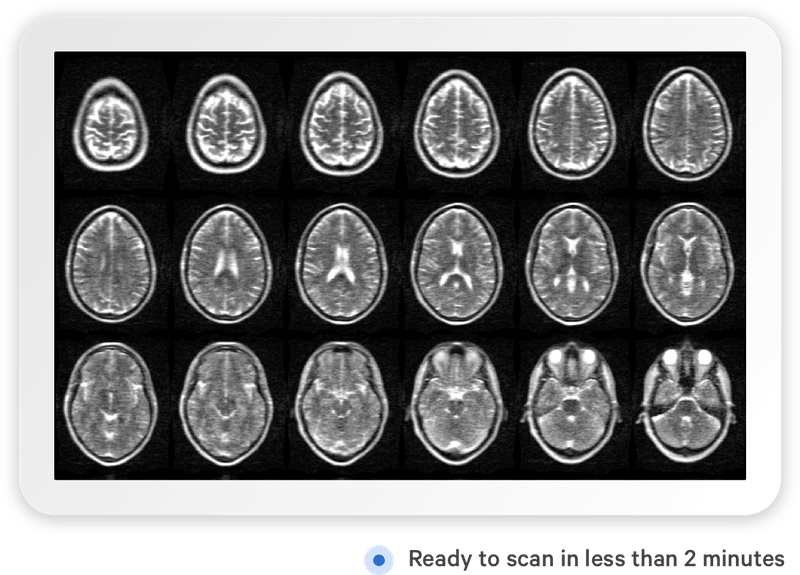

Фото: hyperfine.io

Осенью прошлого года американская компания Hyperfine Research представила свой портативный томограф. Он не в полной мере заменяет обычное МРТ-исследование, сканирует только голову, но может использоваться для экспресс-диагностики инсульта и других проблем, а также в случаях, когда пациент не может позволить себе полное обледование.